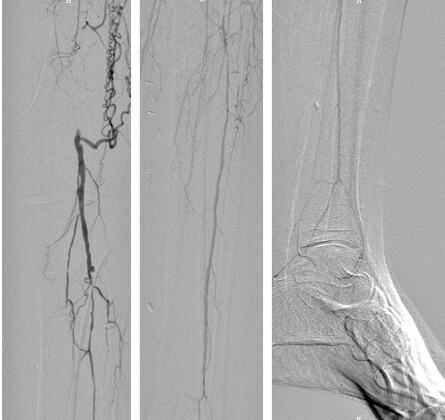

S.U. (geboren 1954; Abb.6) wurde wegen einer trockenen Gangrän der linken Großzehe eingewiesen. In der Umfelddiagnostik zeigte sich ein extrem komplexes Bild der prämaturen generalisierten Arteriosklerose (peripher, extrakraniell, kardial). Bereits in jungen Jahren wurden sowohl an den Beinarterien als auch am Herzen Gefäßeingriffe durchgeführt. Neu diagnostiziert wurde eine hochgradige Verengung der rechten A. carotis interna. Diese musste vordergründig behoben werden. Anschließend wurden komplexe Gefäßeingriffe am linken Bein durchgeführt. Trotz dieser Interventionen konnte der Zeh nicht gerettet werden und wurde entfernt. Im Verlauf heilte die OP-Wunde nicht ab. Der Befund weitete sich aus. Man entschied sich für eine autologe Stammzelltherapie im Bereich des linken Unterschenkels. Damit konnte die Perfusion soweit stabilisiert werden, dass nur noch der benachbarte Zeh amputiert werden musste. Wichtig war, die Ursache der ausgeprägten Gefäßverkalkungen zu ermitteln. Neben eines schlecht eingestellten Diabetes mellitus wurde eine besondere Fettstoffwechselstörung gefunden. Neue diagnostiziert wurde eine ausgeprägte Lipoprotein (a)-Erhöhung. Der Patient wurde deshalb einer Lipidapherese-Behandlung zugeführt, die antilipämische Medikation optimiert. Erst dadurch konnte auch die Gefäßerkrankung stabilisiert werden. Angelegte Bypässe und Stents blieben über den Beobachtungszeitraum offen. Das DFS konnte zur Abheilung gebracht werden.

Abb.6: Angiografiebilder bei PAVK. Im ersten Bild ist ein Verschluss der A. femoralis com. zu sehen.